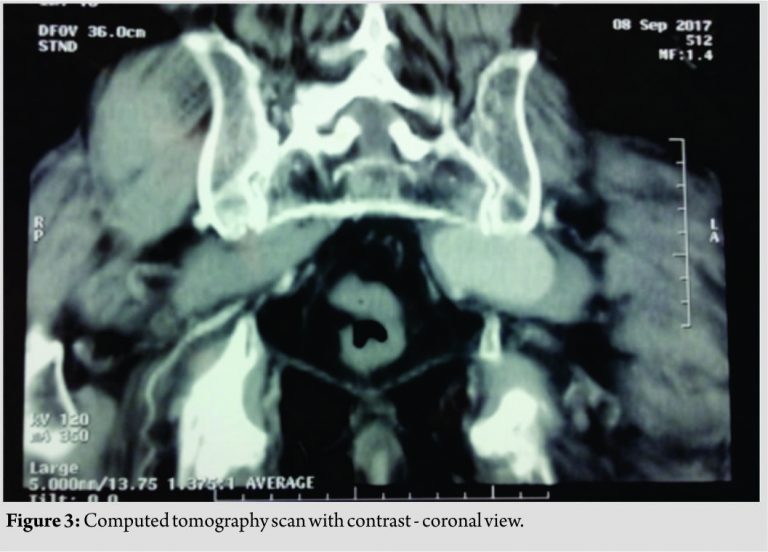

This mass could be either a hematoma or a pseudoaneurysm, considering the previous BMP. To distinguish those two entities, a computed tomography (CT) scan with intravenous contrast of the pelvis was performed, which revealed a left superior gluteal artery (SGA) false aneurysm (Fig. 2 and 3). The patient was referred to the department of vascular surgery of a tertiary center for further evaluation and treatment. Initially, the patient underwent a left internal iliac artery selective angiography, which did not manage to identify the specific arterial branch from where the pseudoaneurysm originated. The next day a percutaneous UGTI was performed, which succeeded to exclude the aneurysm from circulation. The success of the procedure was confirmed by a Doppler ultrasound which showed no arterial flow inside the pseudoaneurysm. At present, 3-week post-procedure, the patient reports significant relief in terms of pain, but still, no improvement of the drop foot is noticed. His follow-up regarding the sciatic nerve function will continue.